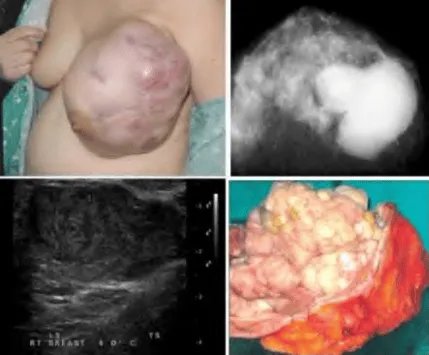

Bướu diệp thể

Phần tiêu đề “Bướu diệp thể”Bướu diệp thể (Phyllodes tumor) là khối u phát triển nhanh, xuất phát từ mô đệm của tuyến vú. Bướu được chia theo mô học làm ba loại: Lành (benign, 60%), giáp biên (borderline, 20%) và ác tính (malignant, 20%).

Phần tiêu đề “Lâm sàng”- Thường gặp ở phụ nữ > 40 tuổi (trong khi fibroadenoma phổ biến hơn ở 20-30 tuổi).

- Kích thước khối thường lớn, phát triển nhanh trong vài tuần đến vài tháng.

- Khối to, chắc, di động, thường không đau.

- Da vùng khối căng, mỏng, có thể giãn tĩnh mạch hoặc loét do khối chèn ép.

- Núm vú hiếm khi bị xâm lấn, nếu có, là dấu hiệu nghi ngờ ác tính.

- Hạch nách sờ thấy trong 20% trường hợp (thường là phản ứng viêm, hiếm di căn).